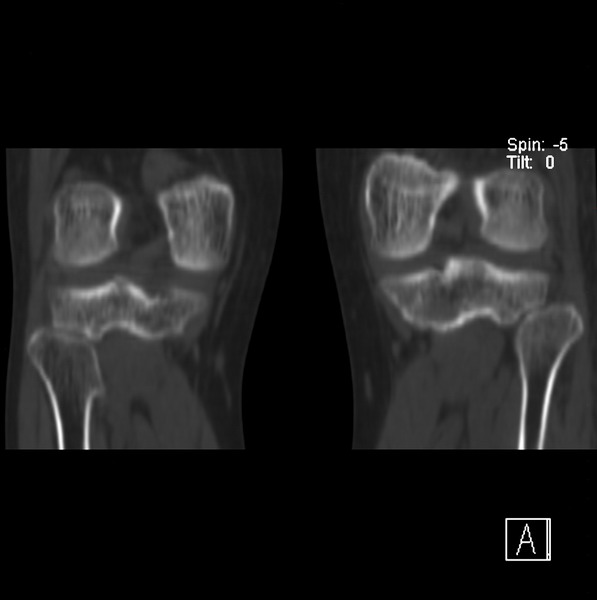

标题: CT21917:右腓骨小头是否骨软骨瘤? [打印本页]

标题: CT21917:右腓骨小头是否骨软骨瘤?

女、43.

不是骨软骨瘤,“牵拽征”,正常变异。有平片吗?

正常变异,“牵拽征”,比目鱼肌牵拽.